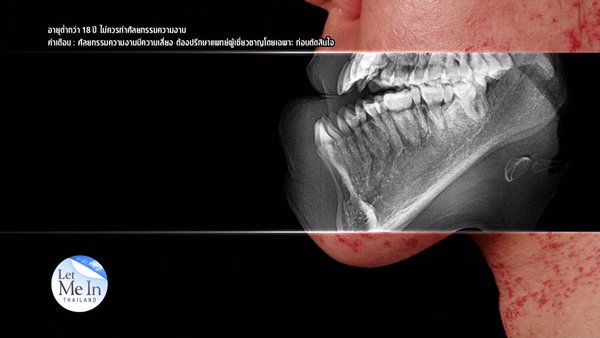

อย่างไรก็ตาม ในตอนแรก ผู้ที่ได้รับคัดเลือกจากรายการให้เป็น Let Me In Thailand คนที่ 3 ของไทย คือ เหวิน พิชญ์พนิต คงถาวรวณิชย์ สาวผู้ป่วยเป็นเส้นเลือดฝอยแตก จนทำให้มีปานแดงตั้งแต่เด็ก และยังมีอีกปัญหาคือฟันไม่สบกัน แต่เมื่อเธอได้รับเลือกให้บินไปศัลยกรรมที่เกาหลีแล้ว แพทย์กลับพบว่า เคสของเหวิน เธอมีผิวหนังที่ผิดปกติ ทำให้การผ่าตัดอาจลำบากมากขึ้น และยังมีเส้นเลือดเข้าไปฝังในกระดูกกราม ทำให้การผ่าตัดครั้งนี้อาจเป็นอันตรายถึงชีวิต ทางทีมแพทย์ได้ปรึกษากันแล้ว สุดท้ายการผ่าตัดของเธอจึงต้องถูกยกเลิกไปอย่างน่าเสียดาย ก่อนที่ เอฟ วลีรัตน์ จะได้รับโอกาสให้เข้าผ่าตัดแทน

ต่อมา เหวิน ได้ถูกเลือกให้เป็น Let Me In Thailand คนที่ 3 ของประเทศไทย จนได้บินไปพบแพทย์ที่เกาหลี แต่แล้วกลับต้องถูกยกเลิกการผ่าตัด เนื่องจากผิวหนังที่ผิดปกติ และมีเส้นเลือดเข้าไปฝังในกระดูกกราม ทำให้การผ่าตัดอาจเป็นอันตรายถึงชีวิต เธอจึงไม่สามารถทำศัลยกรรมพลิกชีวิตในครั้งนี้ได้นั่นเอง... แต่ทางรายการก็ไม่ได้นิ่งนอนใจ และได้ช่วยประสานงานการรักษาของเหวินต่อไป